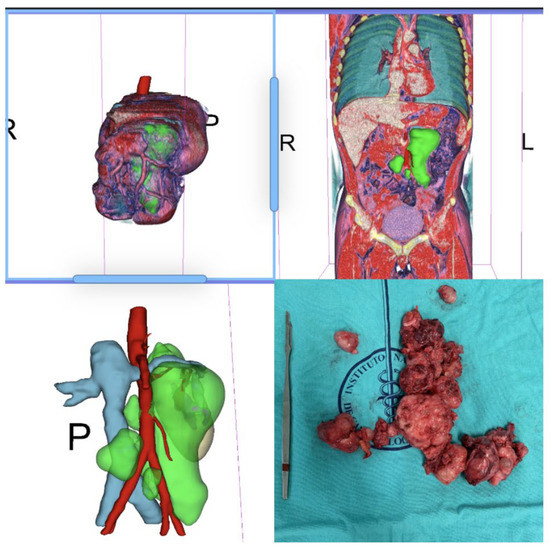

Table 1 summarizes the clinical information of the patients included in this study (n = 60). The median age of all patients was 25.50 (IQR = 17–56). The median size of the residual tumor was 89 cm3. There were no significant differences between the two subgroups. Figure 1, Figure 2, Figure 3 and Figure 4 are examples of prospective cases in which the tumor analyzed pre-operatively with 3D images is totally resected by a young surgeon. No death occurred during the intraoperative and perioperative period in this study.

Figure 3. Para and retro-caval Post-chemotherapy Germ Cell Tumor. The mass displaced the cava without infiltration according CT-rendering and 3D reconstruction. It was excised completely without need for vascular surgery. R means right side; L= left side and P = posterior vision; the green circle show the tumor.